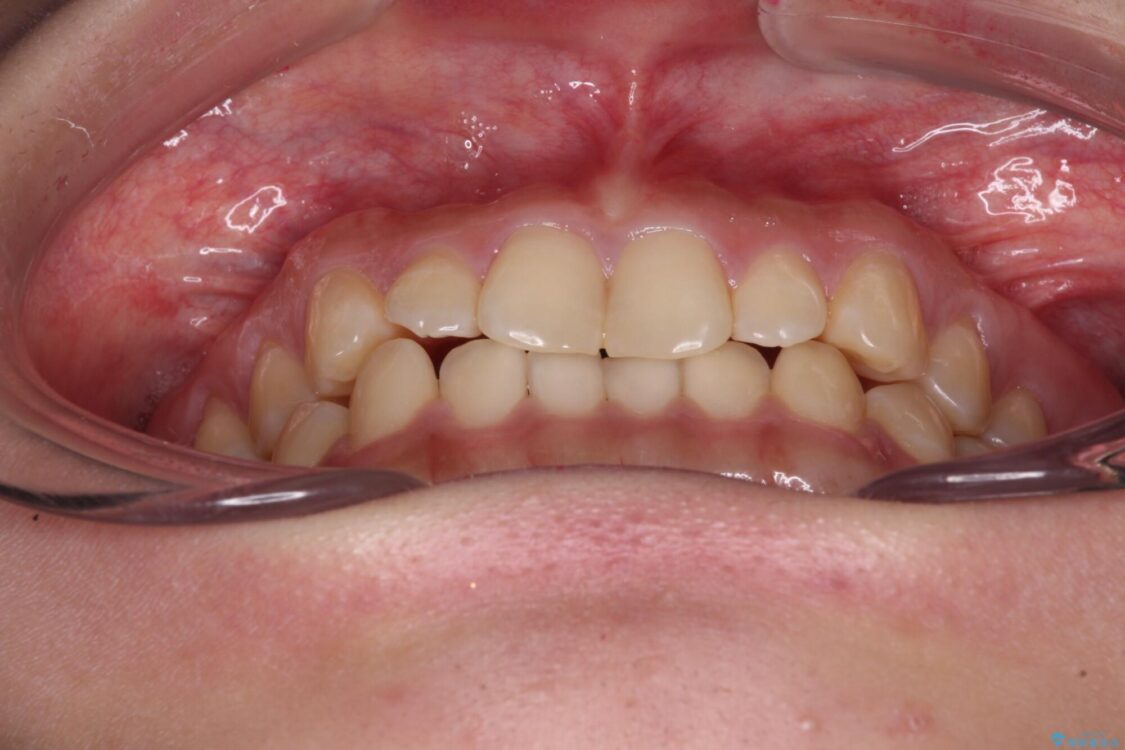

根管治療を行ったままの奥歯と、矯正治療の後戻りを気にして来院された患者様です。

矯正治療の後戻りは軽微であったため、インビザラインの簡易パッケージであるインビザライン・ライトを用いて歯列を整えることとしました。

治療前

• 治療途中の奥歯と矯正治療の後戻り インビザライン・ライトによる矯正治療 治療前画像